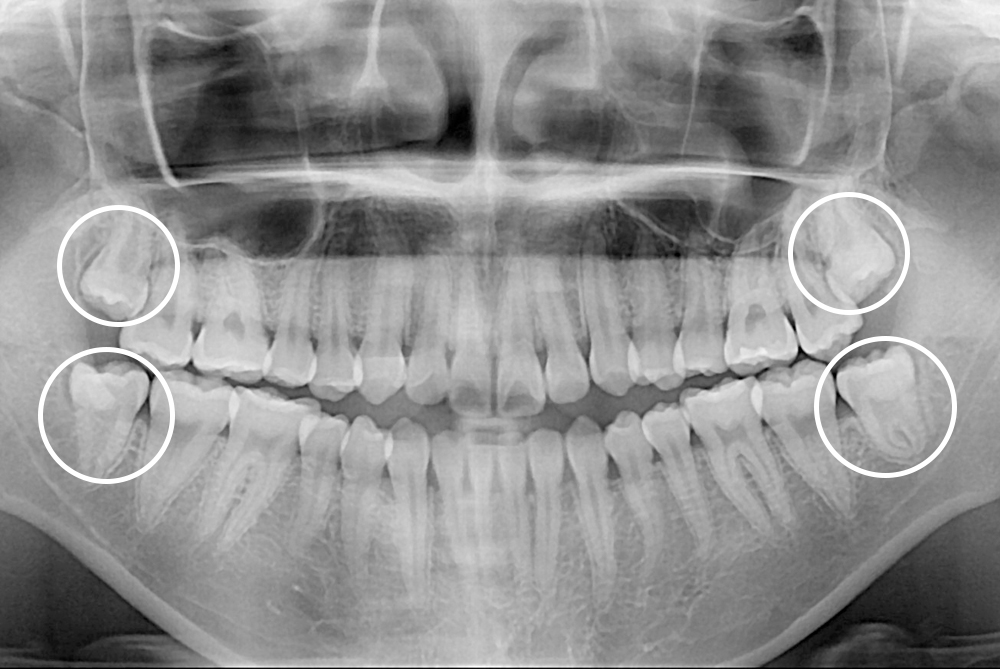

[사랑니] 매복 사랑니 발치

치료전 : 2021-05-03